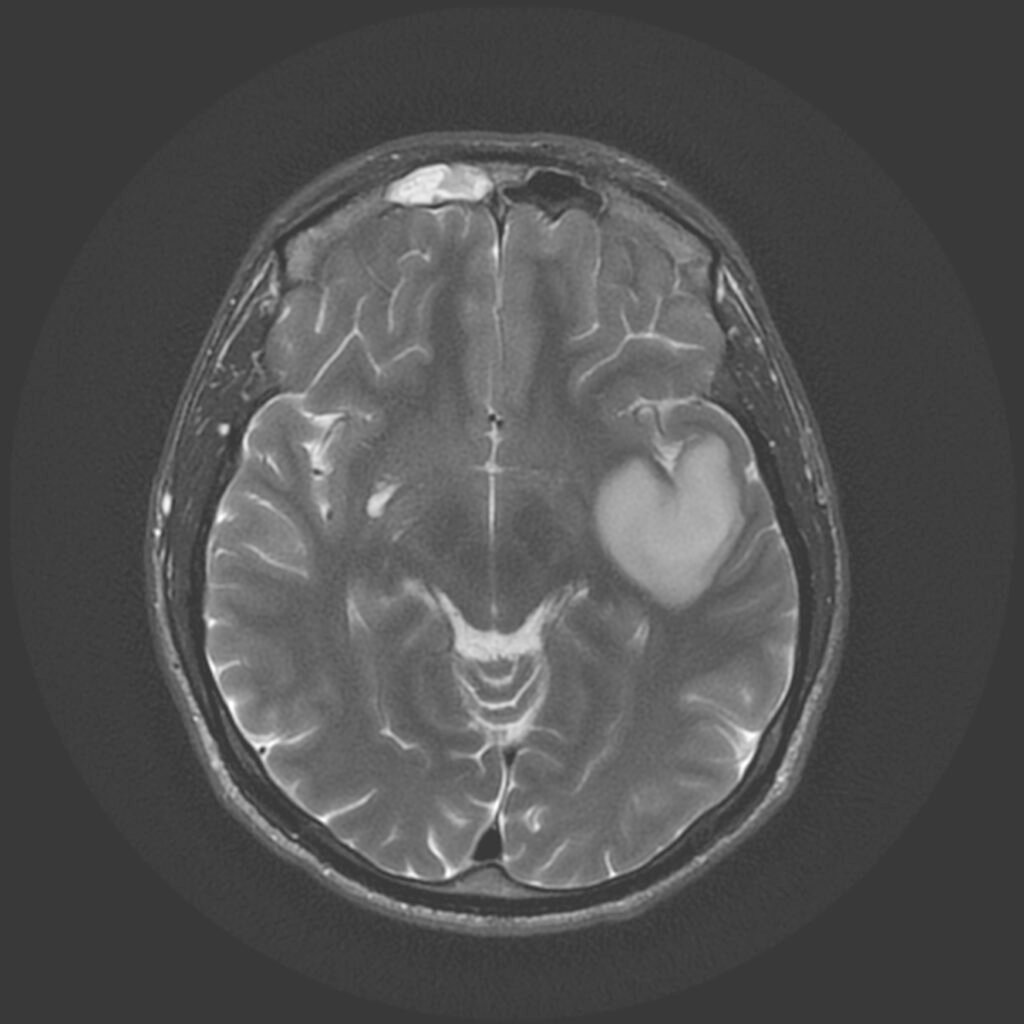

Tumora era bine delimitată, cu priză omogenă de contrast, și are origine din dura mater (foița externă a meningelui) de la nivelul șanțurilor olfactive – porțiunea din baza craniului pe unde trec nervii olfactivi. Aspectul RMN sugerează un diagnostic histopatologic de meningiom – tumoră benignă (în peste 95% din cazuri) .

Intervenția chirurgicală este cea mai bună soluție în asemenea situații, pentru că, deși benignă, tumora va continua să crească și va începe să determine și alte manifestări neurologice (crize comițiale, afectare vizuală, declin cognitiv – demență, etc.). De asemenea, cu cât tumor este mai mare, cu atât mai lungă și dificilă va fi operația, în timp ce pacientul va fi mai vârstnic și, posibil, cu mai multe suferințe cronice asociate. Un aspect care merită menționat este că portiunea posterioară a tumorii ajunge în apropierea celor doi nervi optici, fără a-i comprima (încă!).